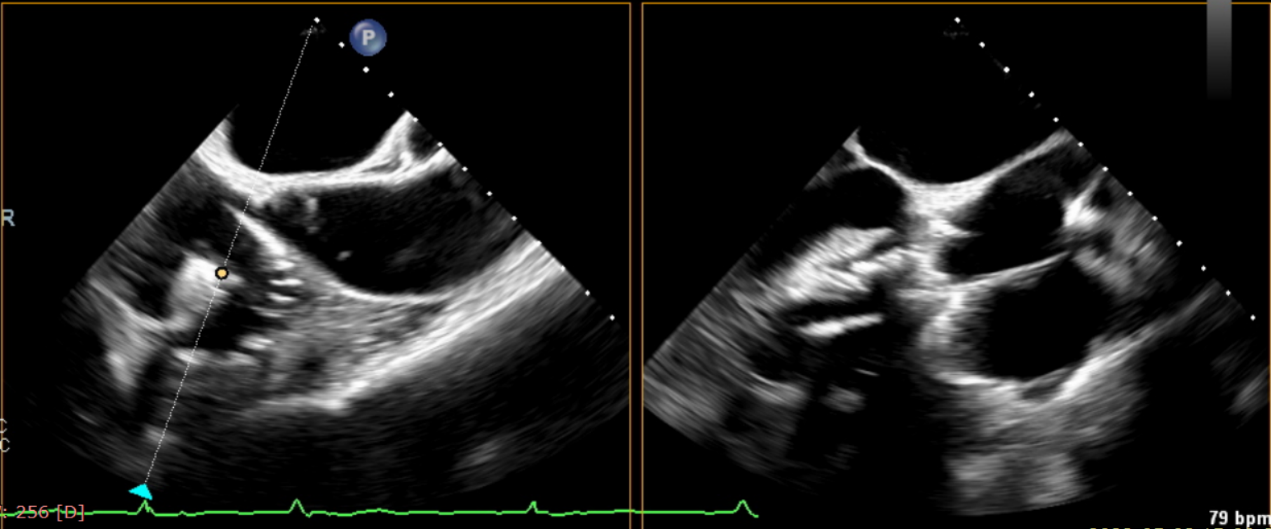

術(shù)后超聲提示無(wú)瓣周漏

術(shù)后超聲提示僅殘余輕微瓣周漏